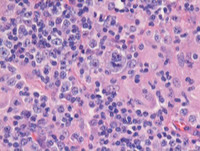

H&E images

Sections from the tonsil shows unremarkable surface epithelium with underlying lymphoid tissue demonstrating destruction of architecture with prominent interfollicular expansion by large clusters and sheets of reactive histiocytes with intervening areas demonstrating plasma cells and occasional immunoblasts. The follicular structures are otherwise morphologically compatible with reactive secondary follicles.